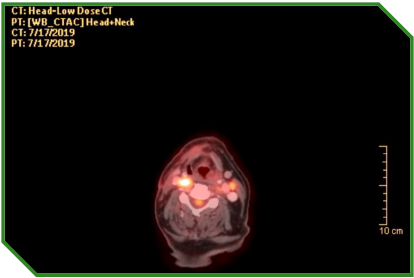

Paciente masculino de 72 anos, portador de carcinoma espinocelular de língua, tratado inicialmente com cirurgia e radioquimioterapia adjuvante, evoluindo com progressão linfonodal e pulmonar. Diante de comorbidades cardiovasculares e fragilidade clínica, recebeu quimioterapia paliativa, seguida da introdução de imunoterapia isolada, após confirmação de expressão tumoral de PD‑L1, permanecendo em acompanhamento clínico e radiológico após suspensão do tratamento por toxicidade imunomediada grave.